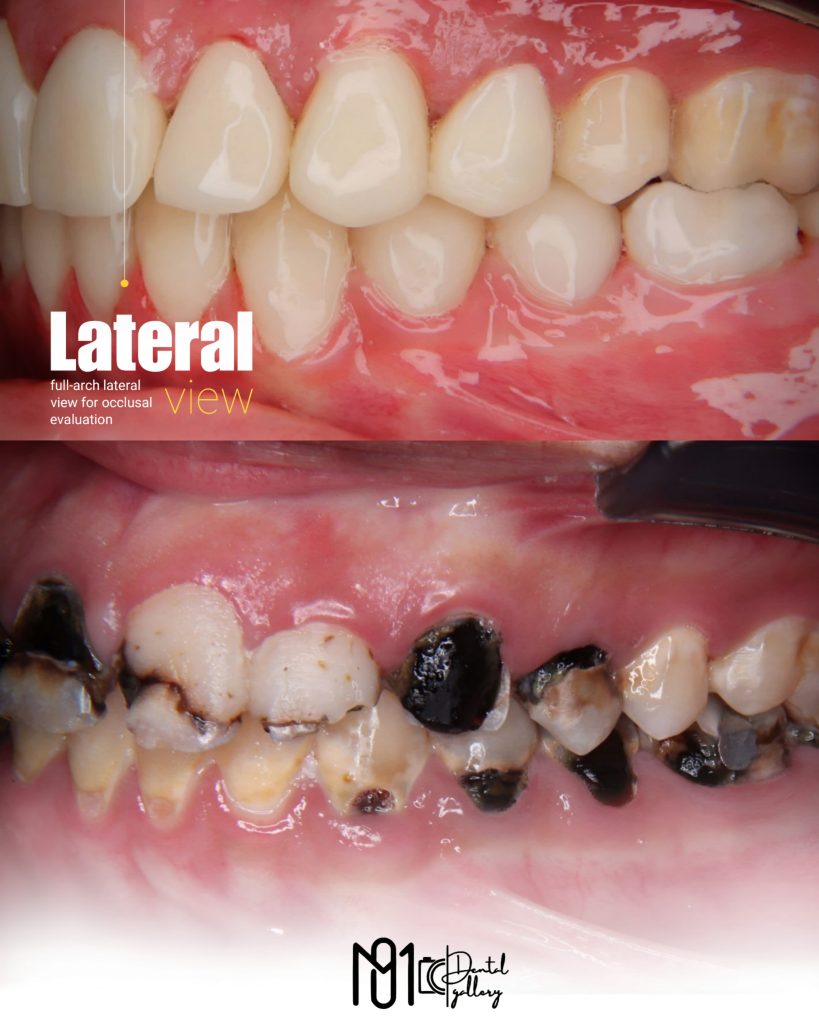

The case involved managing extensive carious lesions across both arches, performing root canal treatments, direct and indirect restorations, and even a periodontal surgical procedure.

I treated multiple deep caries cases using Immediate Dentin Sealing (IDS), performed Composite Resin Restorations (CRR) for both anterior and posterior teeth, and placed temporary restorations to maintain occlusion before the final prostheses.

In total, this case included 23 composite restorations, 7 full coverage crowns, and 2 root canal treatments, all completed between February 10th, 2025 and May 12th, 2025.